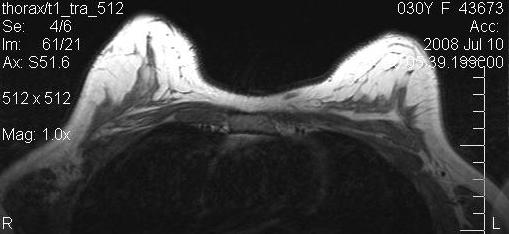

The next two images show the preoperative and postoperative MRI scans of the patient of Figure 6 [Fig. 6] with capsular fibrosis after complete subpectoral placement (Figure 12 [Fig. 12], pre-op), and after implant removal and fat grafting (Figure 13 [Fig. 13], post-op). Remainders of the capsule are not to be seen after the procedure. The amount of fat grafted was only 2/3 of the implant volume. The patient was extremely pleased with the result and did not wish further volume increase.

Figure 12: Preoperative MRI of a patient with capsular fibrosis after complete subpectoral placement

Figure 13: Postoperative MRI of the same patient after implant removal and fat grafting. Remainders of capsule are not to be seen.